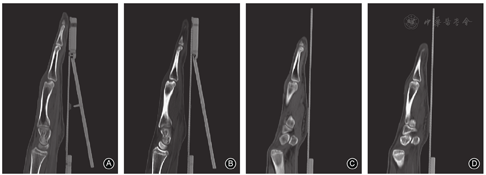

右手X线片示第5掌骨骨折愈合,第3、4掌骨头关节面变平,局部骨小梁中断、低密度透光区,软骨下塌陷、局部骨质硬化,无明显的掌指关节半脱位(图1B)。CT片示右手第3、4掌骨头坏死,背侧见囊状低密度灶、周围局部骨质硬化,关节面皮质骨缺损(图2)。实验室检查:血常规、红细胞沉降率、IL-6、类风湿因子等血清学检查指标正常。诊断为右手第3、4掌骨头缺血性坏死。